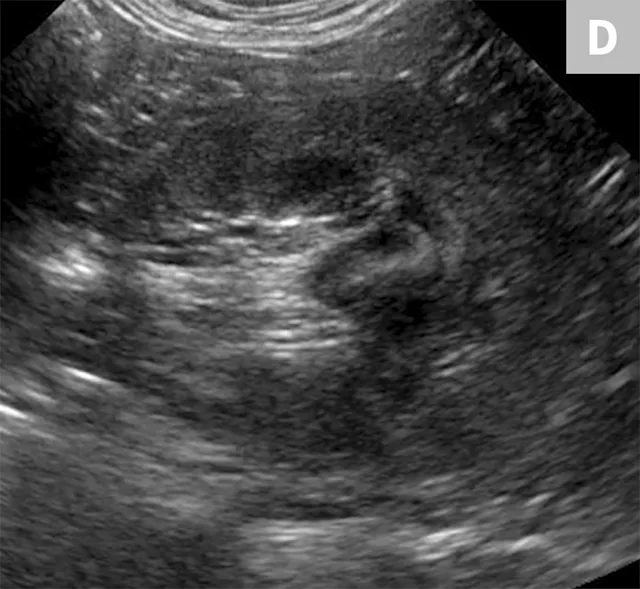

The obstruction can be located at any point of the ureter and can vary in severity. Normal ureters are typically not seen on ultrasonography due to their small size. The easiest way to locate a dilated ureter is to trace the ureter from the renal pelvis. In most cases, the ureter is dilated proximal to the site of an obstruction and tapers to a more normal appearance distal to the site of obstruction. Imaging can also reveal retroperitoneal effusion which can result from ureteritis and possible urine leakage.

Clinical signs associated with ureteral calculi may range from chronic non-specific signs to acute or chronic renal failure. The presence of hydronephrosis can be highly suggestive of a ureteral obstruction (Figure 6).

Differentiation between a complete vs partial ureteral obstruction can be difficult with survey radiography and ultrasonography alone. Antegrade pyelography (nephropyelocentesis with renal pelvic injection of iodinated positive contrast medium using ultrasound guidance) may be useful for documenting a complete vs partial obstruction (Figure 7).11